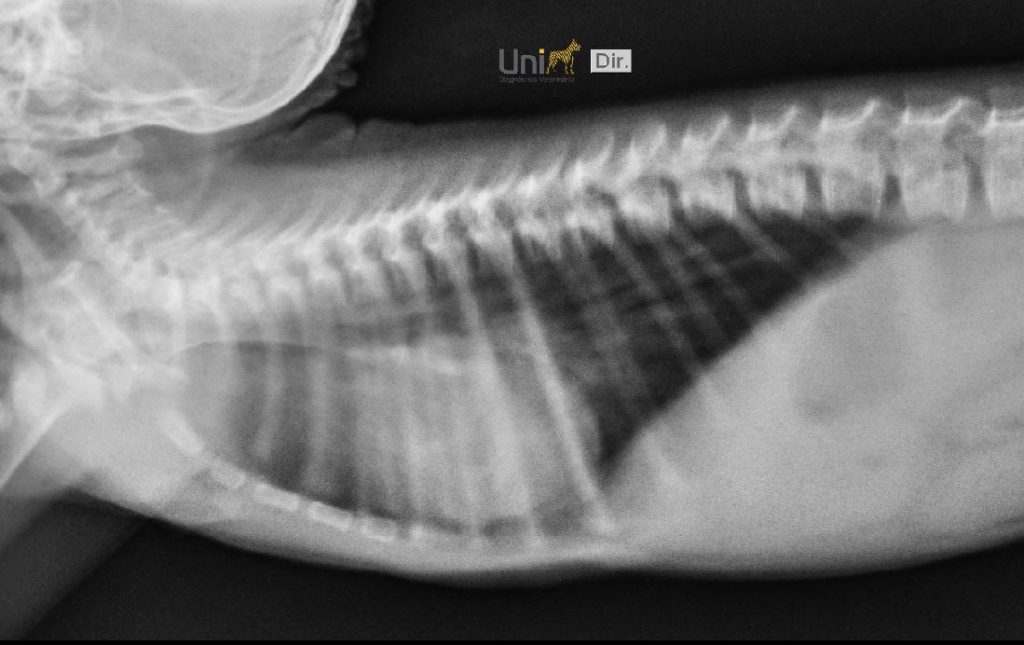

O filhote já passou por exames clínicos e radiográficos e sua saúde geral está estável. Está ativo, com pulmões saudáveis e segue em fase de adaptação alimentar compatível com a idade. “A introdução alimentar começa por volta dos quatro meses. Então, é um processo mais lento e cuidadoso”, completa a bióloga.